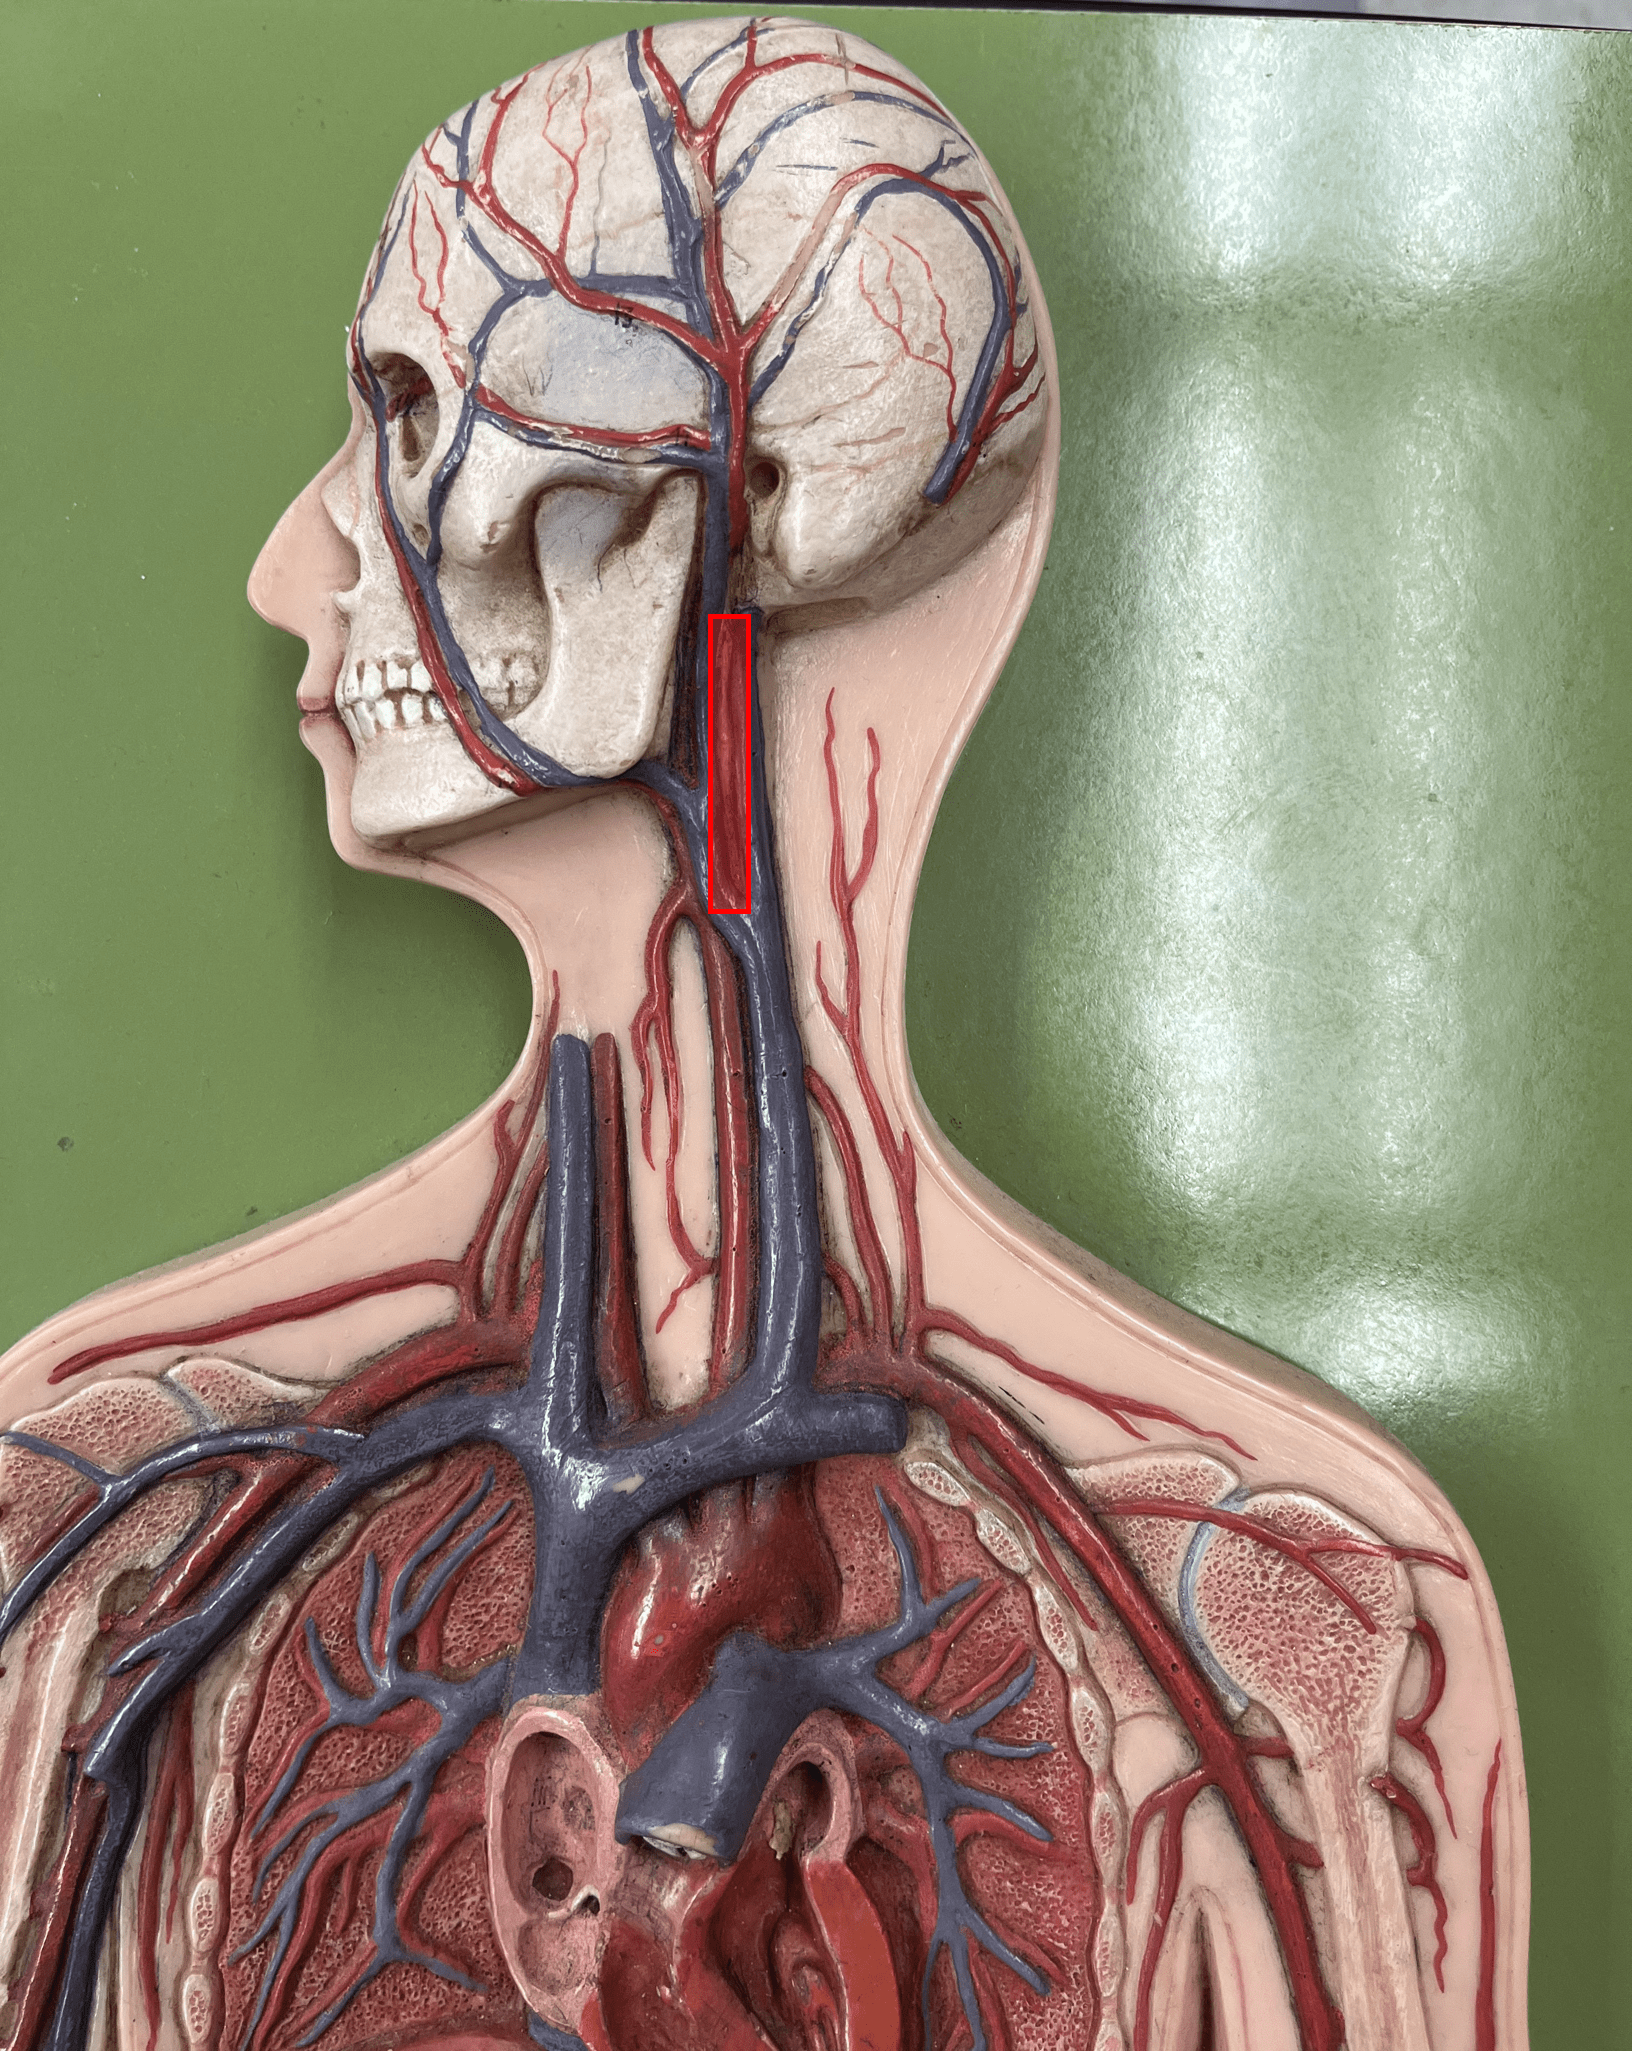

common carotid artery

• An artery of the head and neck.

• Originates from the brachiocephalic trunk (R.) or the aortic arch (L.).

• Supplies the head and neck through its branches.

• Originates from the brachiocephalic trunk (R.) or the aortic arch (L.).

• Supplies the head and neck through its branches.

14

New cards

external carotid artery

• An artery of the head and neck.

• Originates from the common carotid artery.

• Supplies the extracranial structures through its branches.

• Laterally, the anteriormost artery of the neck.

• Originates from the common carotid artery.

• Supplies the extracranial structures through its branches.

• Laterally, the anteriormost artery of the neck.

15

New cards

facial artery

• An artery of the head and neck.

• Originates from the external carotid artery.

• Supplies the skin and muscles of the face.

• Originates from the external carotid artery.

• Supplies the skin and muscles of the face.

16

New cards

maxillary artery

• An artery of the head and neck.

• Originates from the external carotid artery.

• Supplies the teeth, maxilla, oral cavity, and external ear.

• Originates from the external carotid artery.

• Supplies the teeth, maxilla, oral cavity, and external ear.

17

New cards

superficial temporal artery

• An artery of the head and neck.

• Originates from the external carotid artery.

• Supplies the chewing muscles, nasal cavity, lateral face and scalp, and dura mater.

• Originates from the external carotid artery.

• Supplies the chewing muscles, nasal cavity, lateral face and scalp, and dura mater.

18

New cards

occipital artery

• An artery of the head and neck.

• Originates from the external carotid artery.

• Supplies the posterior scalp.

• Originates from the external carotid artery.

• Supplies the posterior scalp.

19

New cards

internal carotid artery

• An artery of the head and neck.

• Originates from the common carotid artery.

• Supplies the cerebrum through its branches.

• Laterally, the middle artery of the neck.

• Originates from the common carotid artery.

• Supplies the cerebrum through its branches.

• Laterally, the middle artery of the neck.

20

New cards

vertebral artery

• An artery of the head and neck.

• Originates from the subclavian artery.

• Supplies the spinal cord, meninges, and neck muscles.

• Laterally, the posteriormost artery of the neck.

• Originates from the subclavian artery.

• Supplies the spinal cord, meninges, and neck muscles.

• Laterally, the posteriormost artery of the neck.

21

New cards

superficial temporal vein

• A vein of the head and neck.

• Drains the chewing muscles and scalp.

• Empties into the internal jugular vein.

• Drains the chewing muscles and scalp.

• Empties into the internal jugular vein.

22

New cards

facial vein

• A vein of the head and neck.

• Drains the skin and muscles of the face.

• Empties into the internal jugular vein.

• Drains the skin and muscles of the face.

• Empties into the internal jugular vein.

23

New cards

occipital vein

• A vein of the head and neck.

• Drains the posterior scalp.

• Empties into the external jugular vein.

• Drains the posterior scalp.

• Empties into the external jugular vein.

24

New cards

external jugular vein

• A vein of the head and neck.

• Drains the facial muscles and scalp.

• Empties into the subclavian vein.

• Laterally, the posteriormost vein of the neck.

• Drains the facial muscles and scalp.

• Empties into the subclavian vein.

• Laterally, the posteriormost vein of the neck.

25

New cards

vertebral vein

• A vein of the head and neck (not shown).

• Drains the spinal cord and neck muscles.

• Empties into the subclavian vein.

• Laterally, the middle vein of the neck.

• Drains the spinal cord and neck muscles.

• Empties into the subclavian vein.

• Laterally, the middle vein of the neck.

26

New cards

internal jugular vein

• A vein of the head and neck.

• Drains the brain, face, and neck.

• Empties into the subclavian vein.

• Laterally, the anteriormost vein of the neck.

• Drains the brain, face, and neck.

• Empties into the subclavian vein.

• Laterally, the anteriormost vein of the neck.